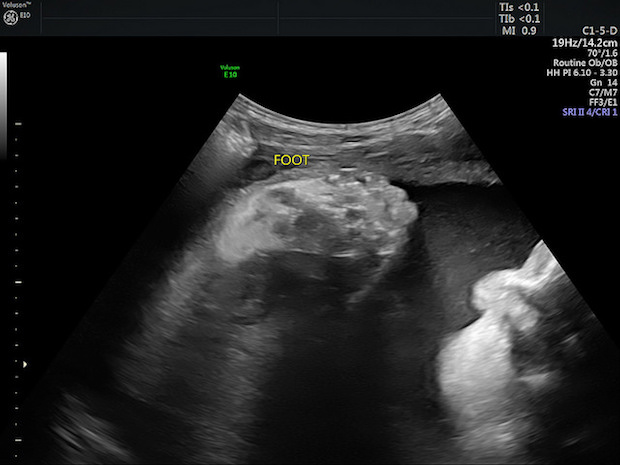

We had an ultrasound around 32 or 33 weeks to check her growth and she was deemed “large for gestational age” at four pounds and nine ounces, which was the 91st percentile for her gestational age.

We have another ultrasound this week to see if she’s still a big girl. Her size is likely due to the gestational diabetes. Once we know more about her size, we will go from there in terms of deciding on delivery options.

I definitely think you will feel SO MUCH BETTER when your iron levels get to a normal level! I am so excited for my first little grandbaby to enter the world, and I truly can’t wait to meet her in person!!!!! Ultrasounds are nice… however, thinking of actually holding her is making me feel beyond excited!!!